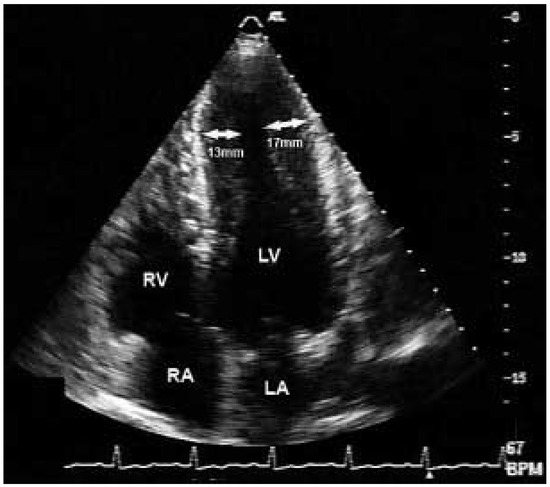

Apikale Hypertrophe Kardiomyopathie—Vom EKG zur Diagnose

by Susanne Buchholz and Thomas Herren

Cardiovasc. Med. 2005, 8(5), 204; https://doi.org/10.4414/cvm.2005.01099 - 27 May 2005

Viewed by 129

Abstract

Der 54jährige, aus Sri Lanka stammende Patient verspürte bei seiner Tätigkeit als Landwirt eine zunehmende Müdigkeit unter Belastung sowie ein «Schweregefühl» in der Brust [...] Full article

Show Figures

Figure 1